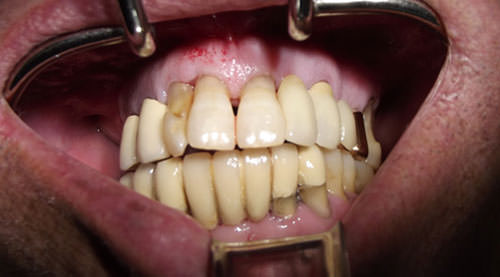

Paciente masculino, de 62 años de edad con diabetes tipo II pero debidamente controlado. Presentaba los dientes 14, 13, 12, 21, 23, 25, 26 del maxilar superior con marcada enfermedad periodontal y movilidad de los mismos. El paciente refirió problemas en la masticación por la movilidad que presentaba, además de halitosis continua y dolor en el 26, presentando una estética insatisfactoria (Fig.1).

Fig. 1

Foto clínica preoperatoria